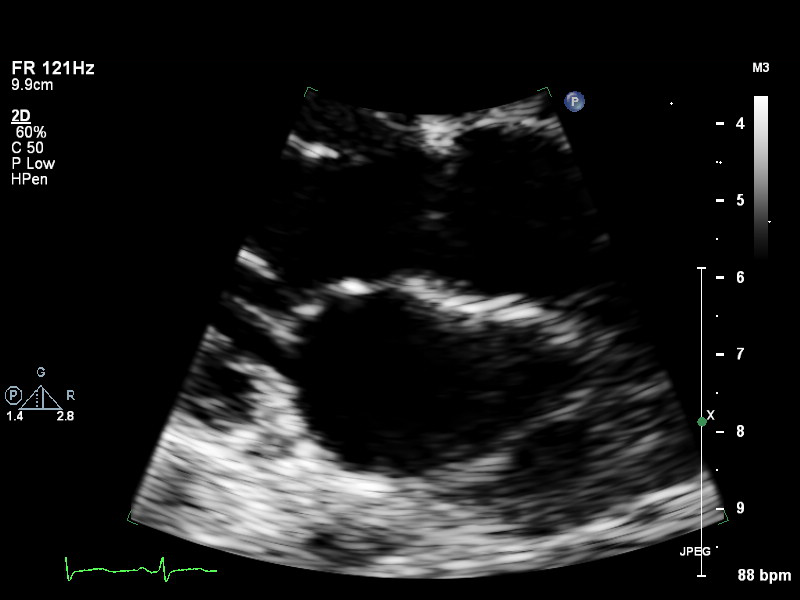

ImageView NameDescription

a4ch-full a4ch-full Apical 4-chamber showing the full depth of all four chambers (no LV/RV focus)

a4ch-ias a4ch-ias Apical 4-chamber, focused on the inter-atrial septum

a4ch-la a4ch-la A4CH with Doppler near MV/LA or 2D covering full LA, not full LV

a4ch-lv a4ch-lv A4CH covering the whole depth of the LV, not the whole depth of the LA

a4ch-ra a4ch-ra Apical 4-chamber focused on the right atrium, or colour Doppler on TV/RA

a4ch-rv a4ch-rv Apical 4-chamber focused on the right ventricle